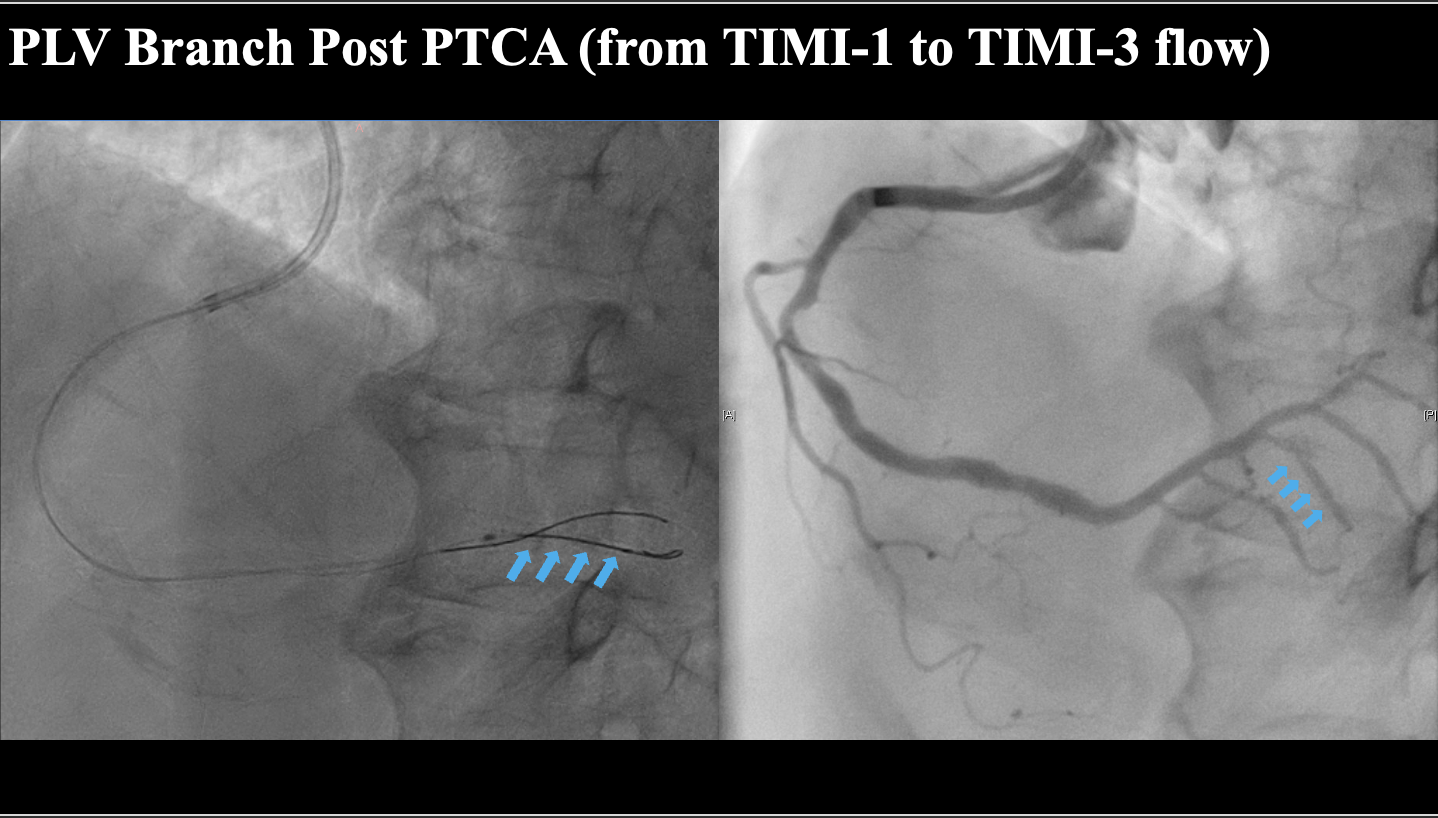

Dualaccess via right radial and right femoral arteries was established. A 7Fr SAL1.0 guiding catheter was used for the RCA, and a diagnostic catheter forcontralateral injection of the LCA. Based on ECG and clinical findings, initialpercutaneous transluminal coronary angioplasty (PTCA) was performed on the PLVbranch using a 2.0 mm semi-compliant balloon, restoring TIMI-3 flow.Despiteexhaustive review of the RCA angiogram, the PDA ostium remained elusive. Toaddress this, a real-time intravascular ultrasound (IVUS)-guided technique wasemployed to systematically identify all side branches, ultimately pinpointingthe PDA ostium with precision. A Finecross microcatheter and UB3 guidewire wereused to create an entry into the PDA, overcoming mild resistance. The UB3guidewire successfully established the entry, and a runthrough guidewire wasadvanced through the chronic total occlusion (CTO) lesion.Serialballoon dilations were performed with 2.0 mm and 2.5 mm semi-compliantballoons. IVUS assessment indicated vessel diameter between 2.0–2.5 mm. A 2.5mm B.Braun Sequent Please Neo drug-coated balloon was used to treat the targetlesion, resulting in an excellent angiographic outcome.